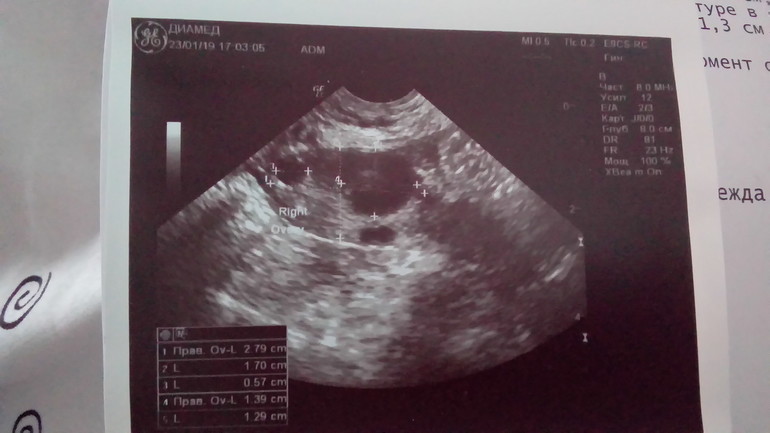

Алёна в Зачатие 7 лет ЖТ? Фолликулометрия Похоже на Желтое тело? Посмотрите еще 20 записей на эту тему Отменить Ответить Кристина Похоже на фолликул, слишком ровные края и цвет. 26.01.2019 Ответить Алёна Узистка утверждала, что это ЖТ и жидкость позади матки есть, а овуляцию чувствовала 3 дня до УЗИ. Я раньше не видела на фото как выглядит ЖТ, фото не делали. 26.01.2019 Ответить Кристина Ей конечно лучше было видно по узи, но по снимку не очень на жт похоже. 26.01.2019 Ответить Алёна Я тоже по другому его представляла, а посередине внутри его что это светлое тогда? 26.01.2019 Ответить Овуляция и Фолликулометрия/узи Узи Чаты Беременных Выберите чат: Январята-2026 Февралята-2026 Мартята-2026 Апрелята-2026 Майчата-2026 Июнята-2026 Июлята-2026 Августята-2026